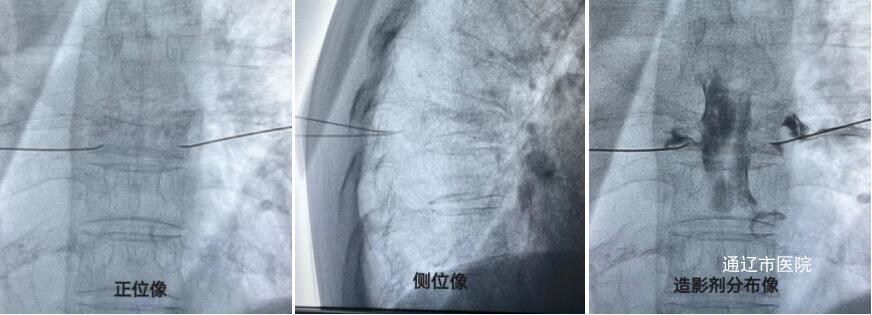

结合吴阿姨病史及全面评估体征后,疼痛科制定了“胸脊神经根射频脉冲术”这一针对性诊疗方案。在介入导管室医护人员的通力配合下,手术顺利完成。术后,吴阿姨表示疼痛明显减轻,脸上露出幸福的笑容,并向我院医护人员送去了“医术精湛、医德高尚”字样锦旗。

三、脉冲射频治疗术是一种经皮穿刺微创介入治疗技术。此项治疗方法主要是在影像指导下,通过脉冲电流作用与神经根靶点,使病变神经、肌肉或组织松解、调理和促进局部炎症吸收进而改变神经之间的信息传递,反馈性地调节神经的电流或传导物质,达到缓解疼痛的目的。具有安全性高、创伤小、治疗部位确切、并发症少的特点。一般可以用于各种疼痛性疾病,包括脊柱源性疼痛疾病、头痛、腰椎管狭窄症等。